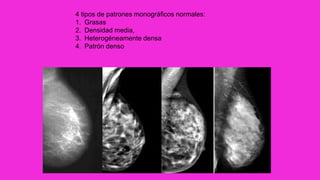

4 tipos de patrones monográficos normales:

1. Grasas

2. Densidad media,

3. Heterogéneamente densa

4. Patrón denso